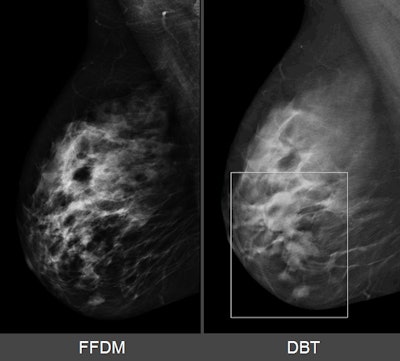

Breast lesion as it appears on 2D mammography (left) and SenoClaire 3D mammography (right). Images courtesy of GE Healthcare.

Breast lesion as it appears on 2D mammography (left) and SenoClaire 3D mammography (right). Images courtesy of GE Healthcare.GE received FDA approval to perform screening exams with two 2D craniocaudal views and two 3D mediolateral oblique views. Because the system in 3D mode delivers no more radiation dose than when in 2D mode, there is no increased radiation to patients, Tabaka said.